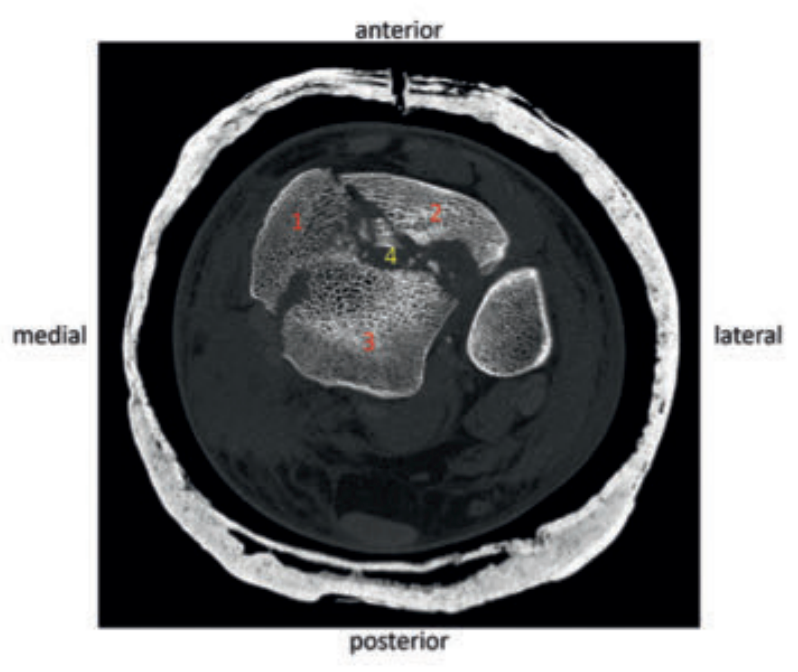

病例1在受伤后送往医院急诊,首先进行了跨踝关节外固定架。尽管患者初始存在Ⅱ度闭合性软组织损伤,但由于及时进行了复位并植入外固定架,未需实施筋膜间室切开术。在术前CT图像中,可清晰观察到3个主要骨折块及1个中央粉碎区。通过及时植入外固定架,可恢复关节位置,并有效避免软组织损伤进一步加重。

待软组织状况改善(出现 “皮肤皱纹征”)后,开始对患者进行手术治疗,首先处理腓骨(遵循 “先处理腓骨” 原则)。术中检查发现韧带联合存在不稳定情况。

术中三维CT 扫描确认骨折达到解剖复位,内植物位置良好。术后影像学检查证实骨折解剖复位,内植物位置正常。患者术后恢复过程顺利,关节功能恢复良好。